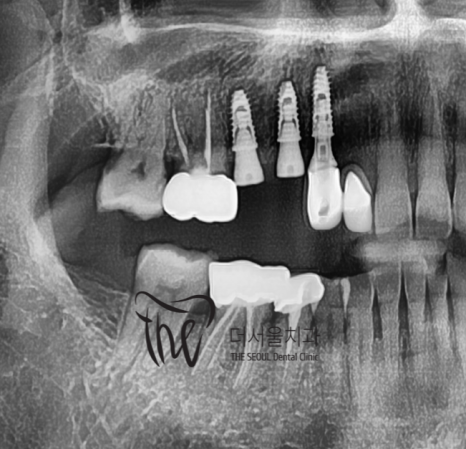

결국.. 3개의 임플란트 시술을 결정내립니다.

좁은 치조골 및 폭경이 충분하질 않았으며,

3개씩이나 되는 implant fixture 들을

한번에 심어야 되는데.. 그것도 나란히요.

쉽지 않았으나, 해냈습니다.

그것도, 원래 있었던 치아마냥 똑같이

재현을 해드리면서 시술 종료!